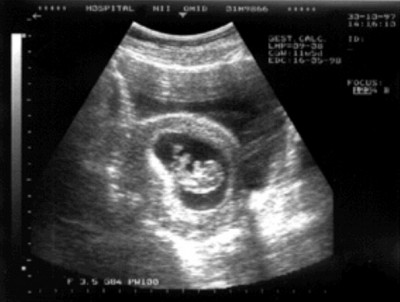

Так выглядит снимок УЗИ на сроке 16-18 недель беременности